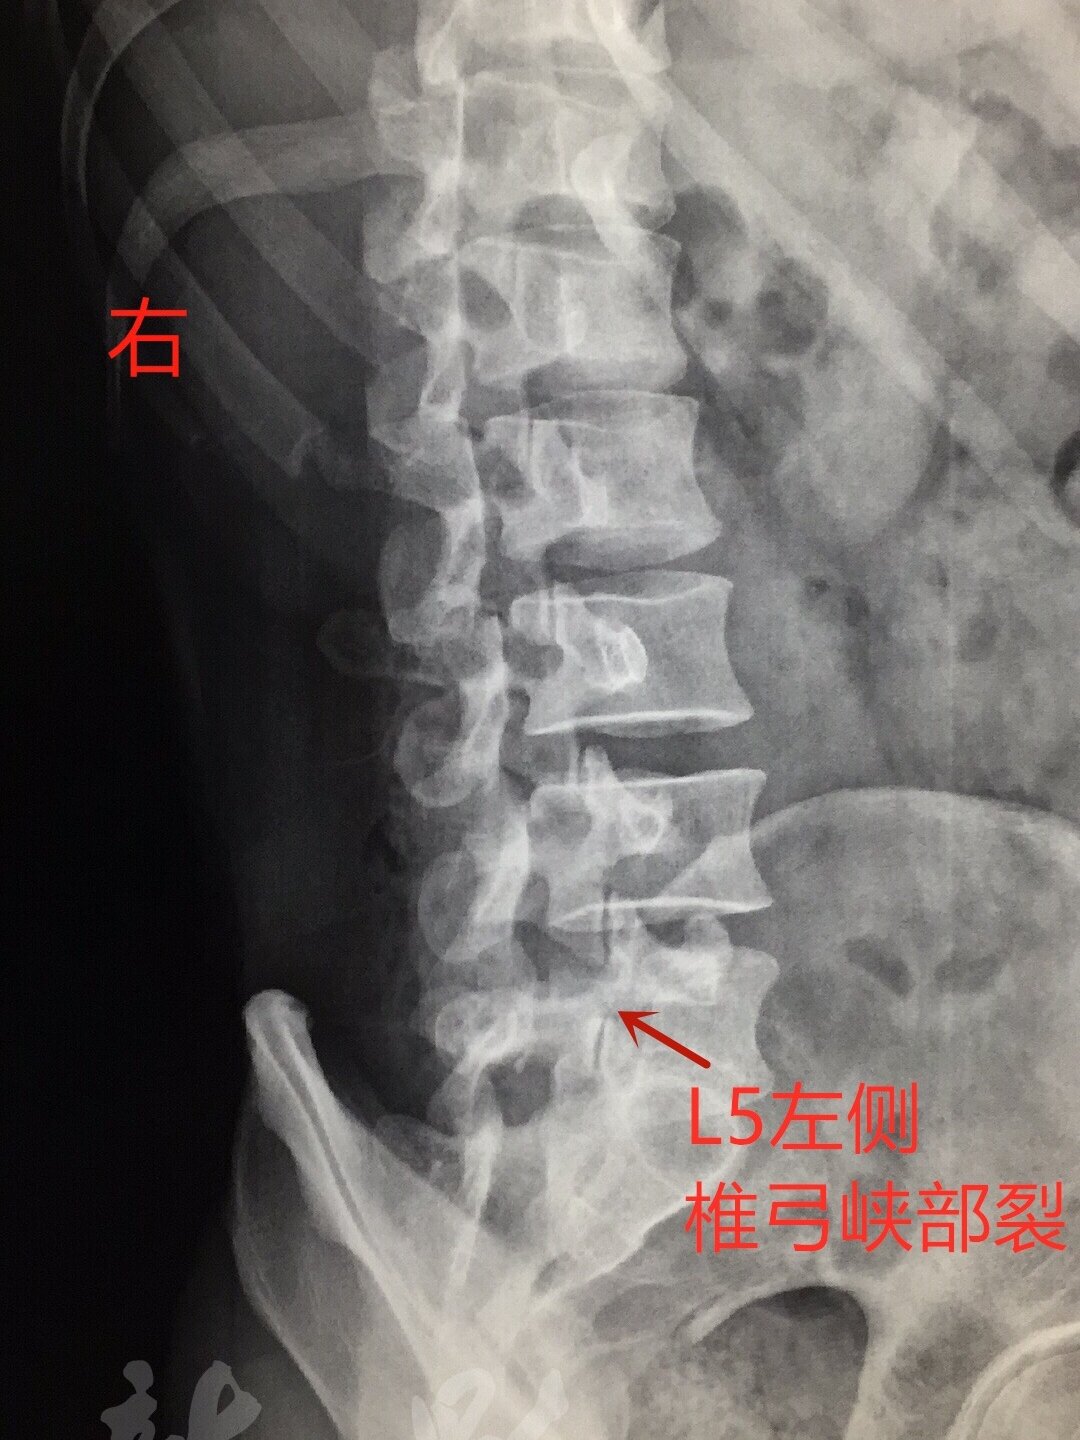

腰椎椎弓峽部裂

图片尺寸1080x1440